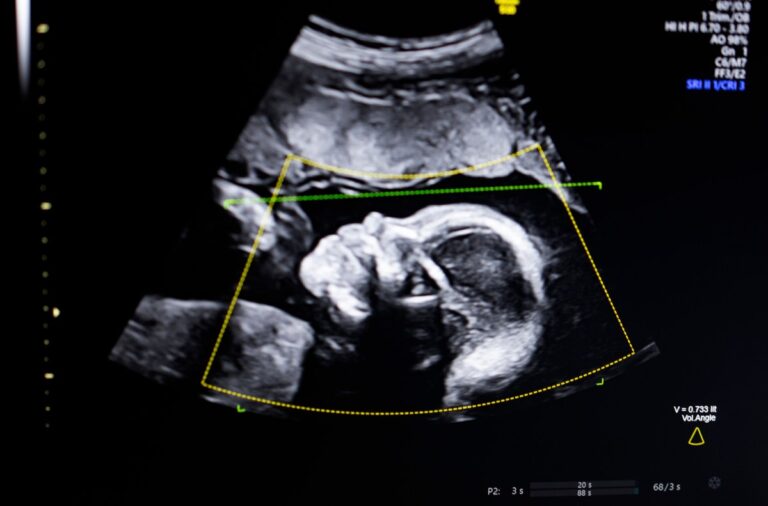

O produto da Biotics AI é um avanço tecnológico que utiliza inteligência artificial para analisar imagens de ultrassom e fornecer informações precisas sobre o desenvolvimento fetal. Com isso, é possível identificar possíveis problemas de forma precoce, permitindo um acompanhamento mais detalhado e um tratamento mais eficaz.

Além disso, a tecnologia também oferece uma experiência única para as gestantes. Com o uso de realidade aumentada, as imagens do ultrassom se tornam mais nítidas e detalhadas, permitindo uma conexão mais profunda entre a mãe e o bebê. Essa inovação pode trazer benefícios emocionais para as futuras mamães, que poderão ver seus bebês de forma mais clara e realista.